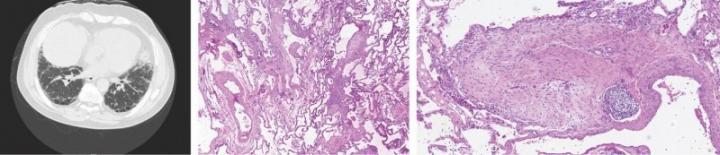

LOS ANGELES (March 20, 2019) -- A protein associated with cancer growth appears to drive the deadly lung disease known as idiopathic pulmonary fibrosis, according to new research from Cedars-Sinai. The discovery, made in laboratory mice and human tissue samples, may have implications for treating the disease using existing anti-cancer therapies that inhibit the protein PD-L1.

Idiopathic pulmonary fibrosis is a chronic, progressive lung condition of unknown cause that affects more than 100,000 people in the U.S. It consists of fibrosis--a buildup of fibrous scar tissue--that eventually robs the lungs of the ability to transport oxygen to the bloodstream. Although the disease progresses at variable rates, most patients die within five years after being diagnosed, according to the National Institutes of Health.

The study focused on cells known as fibroblasts, which produce proteins to help build the extracellular matrix--a meshwork of macromolecules that provides structure and biochemical support for cells in the body's tissues. In idiopathic pulmonary fibrosis, defective fibroblasts invade normal lung tissue and generate excessive deposits of fibrous (scar) tissue that progressively impairs lung function.

In examining lung tissue samples from idiopathic pulmonary fibrosis patients, the study's investigators found that the invasive fibroblasts secreted high levels of PD-L1, a protein found on normal cells that prevents immune cells from attacking them. By "masquerading" as normal cells, the invasive fibroblasts could evade destruction by the body's immune system.